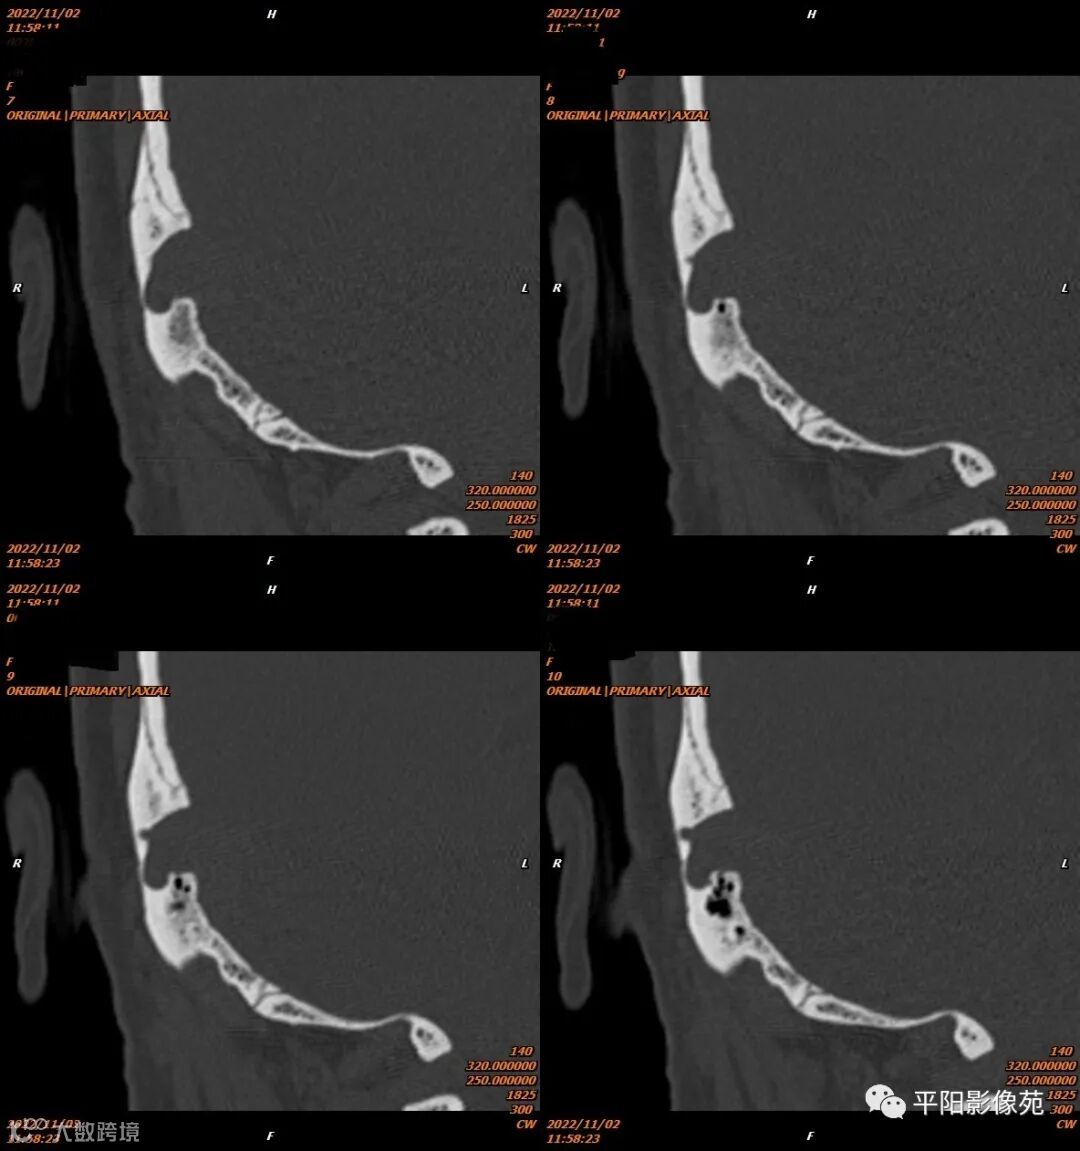

影像表现

影像表现:乙状窦局限性扩大,向右侧膨出,压迫右侧颞骨凹陷,前方乳突气房骨壁缺损。

影像诊断:乙状窦憩室